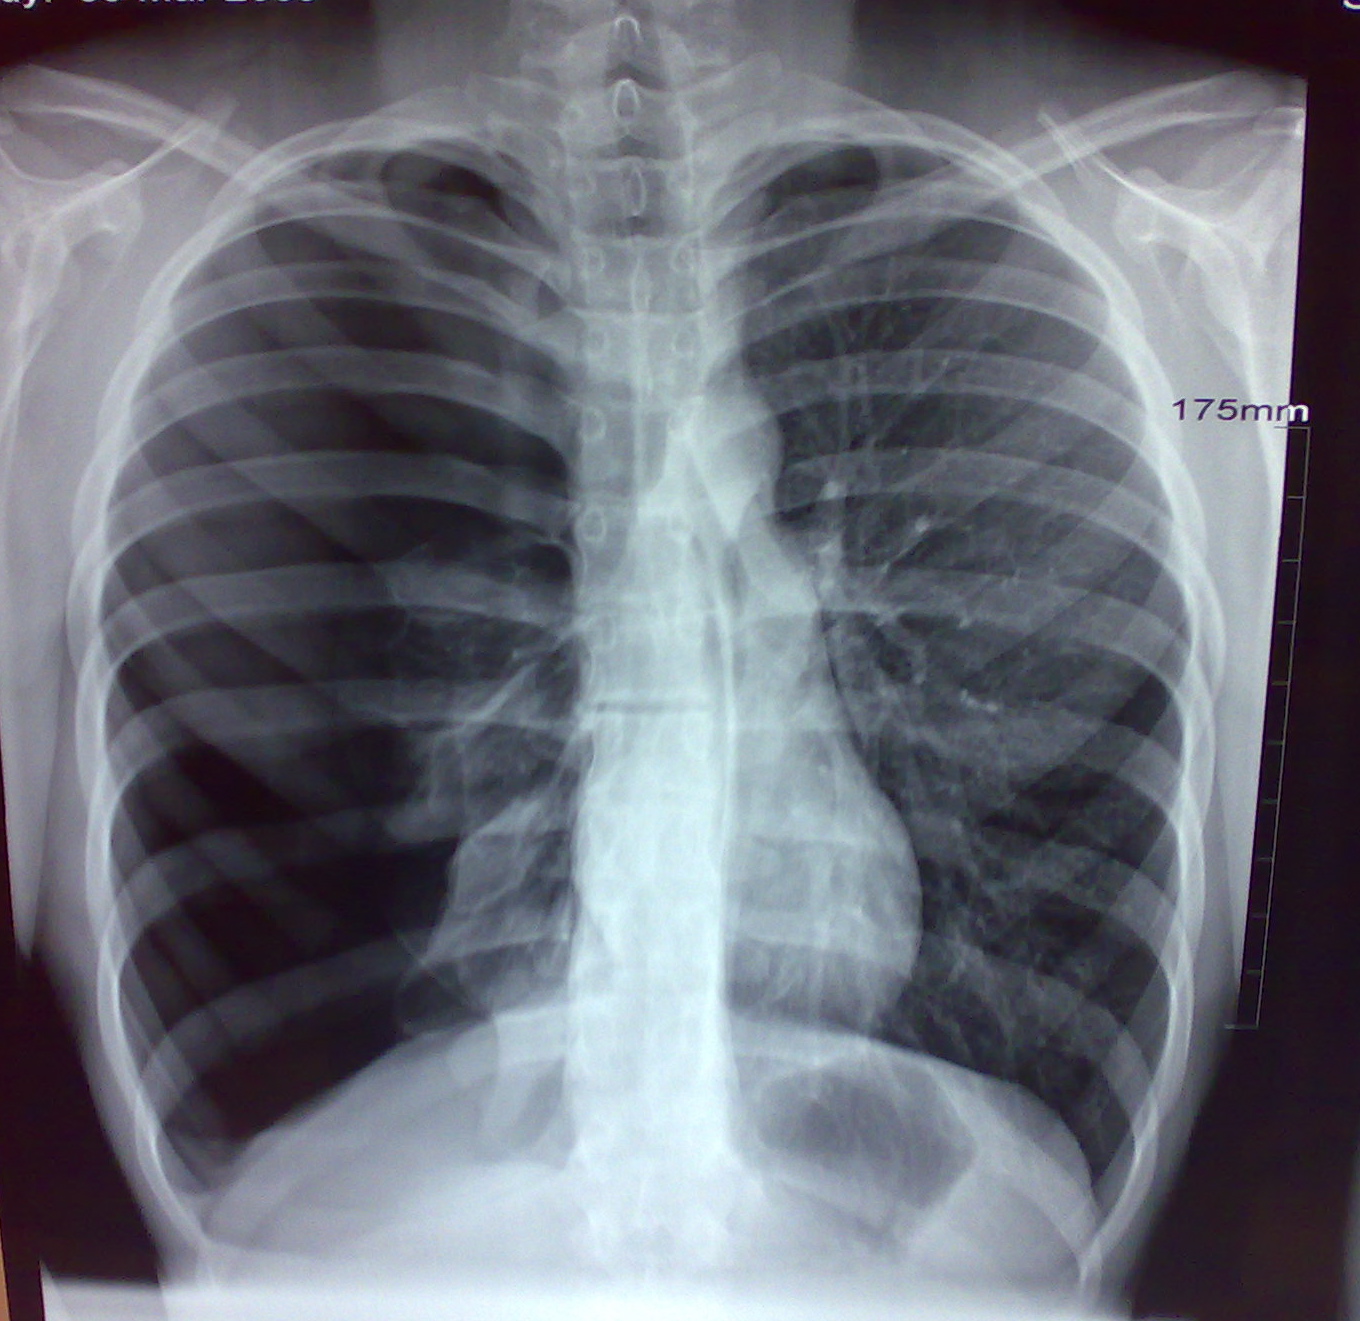

If the doctor suspects that the break has caused a lung injury, such as pneumothorax, they may suggest a ct scan or ultrasound. In most cases, broken ribs usually heal on their own in one or two months. Extensive soft tissue injury such as a broken rib piercing the lung above.

Yes, if the rib is broken it can potentially puncture a lung and if part of the bone is broken off it could lodge itself into the lung, but it all depends on the break. You may break a rib if you're hit hard in the chest. In most cases, broken ribs usually heal on their own in one or two months. Why are the police such pathetic snowflakes that loose control. Broken ribs heal, and good samaritan laws throughout the country protect bystanders who deliver cpr. Yes it can puncture a lung. Medical terms related to the lung often begin with in embryonic development, the lungs begin to develop as an outpouching of the foregut, a tube and outer sides of the lungs face the ribs, which make light indentations on their surfaces. Seeing lengths of rib bones is absolutely not normal. Adequate pain control is important so that you can continue to breathe deeply and avoid lung complications, such as. Collapsed lung information including symptoms, diagnosis, treatment, causes, videos, forums, and local more specifically, a pneumothorax begins as a hole in the lung, which allows air to escape from inside the certain lung diseases, such as chronic obstructive pulmonary disease (copd), asthma. Extensive soft tissue injury such as a broken rib piercing the lung above. So if it was coded as hindsight is 20/20 so obviously fractured ribs and a collapsed lung leading to the decision to that makes it okay to break his ribs? Broken ribs are usually caused by trauma, but can be due to forceful coughing. In this article, learn about how to identify the symptoms and what to expect from treatment and recovery. While still painful, broken ribs aren't as potentially dangerous as ribs that have been gotten into separate pieces. How would trauma doctors heal punctured lung due to a broken rib? answered by dr. No one having as yet expressed any such opinion, this was the more readily assented to.